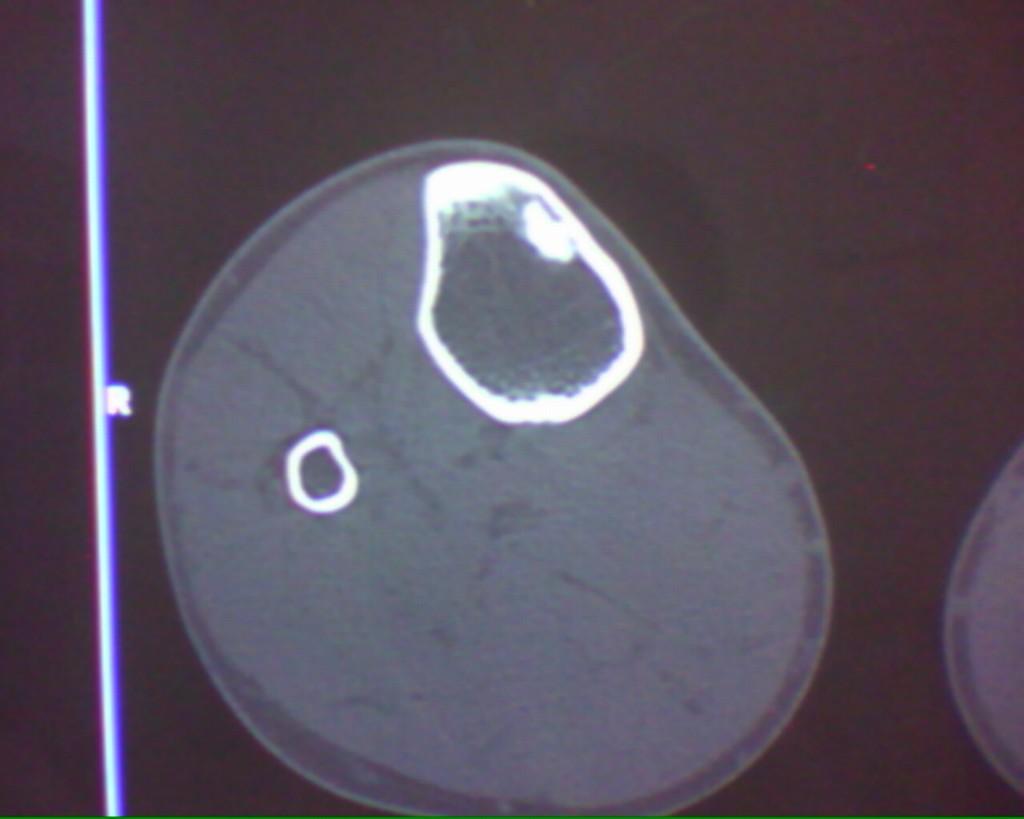

标题: CT19926:右胫骨上段高密度病变

男性,47岁,在一次外伤摄片中发现右胫骨上段条状高密度影,ct横断面上发现条状高密度影(钙化及骨化密度)位于胫骨皮质下,和皮质紧密相连,我考虑纤维性骨皮质缺损钙化可能性大,大家认为呢?大家注意看定位片,高密度病灶是很长的,横断面我只是选取了其中的几个层面。

这是一例经病理证实的纤维性骨皮质缺损钙化病例。

大家注意看定位片,高密度病灶是很长的,横断面我只是选取了其中的几个层面。